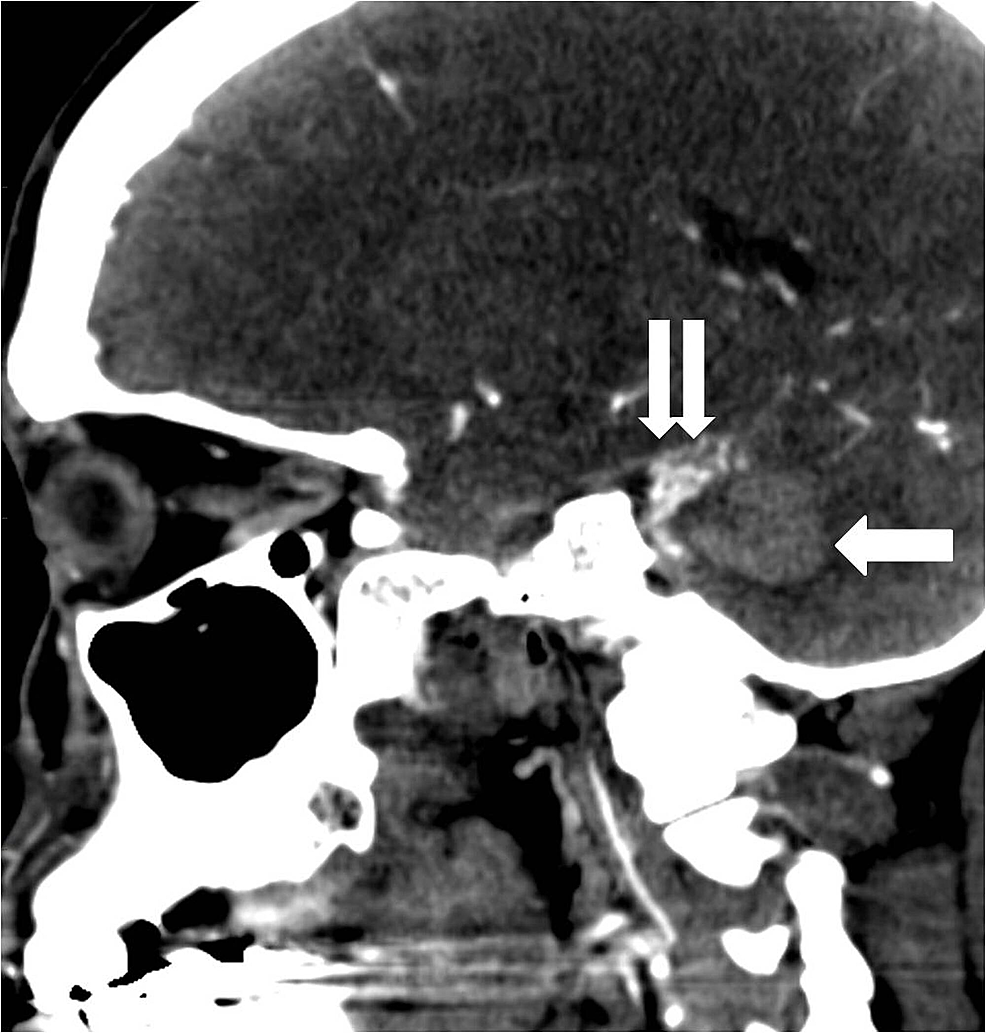

A 39-year-old female with a history of posterior fossa AVM, AIDS, and hypertension presented with headaches, dizziness, blurry vision, and left-sided facial numbness. She had a previous history of hemorrhage from an AVM in the posterior fossa which was treated with a partial embolization two years prior. She was scheduled for a resection of the AVM at that time but was lost to follow up. Physical exam showed no abnormalities on admission. CT scan of the head showed an acute parenchymal hemorrhage in the inferior left cerebellum (Figure 6).

CT angiogram (CTA) showed a left posterior fossa vascular malformation that had remained largely unchanged from the prior admission two years earlier (Figure 7).

The patient was admitted for further workup of the intracranial hemorrhage. Cerebral angiography on day two of admission showed an AVM measuring 1 cm by 2 cm predominantly supplied by the left superior cerebellar artery as well as the left anterior inferior cerebellar artery (Figure 8).